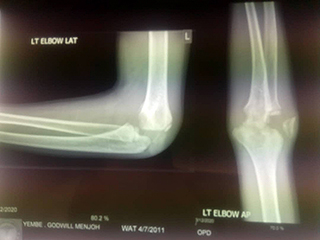

Mitte März 2020 konnte die Mutter schlussendlich den 62 km langen Weg ins Spital nach Kumbo auf sich nehmen. Nach einer Röntgenaufnahme wurde festgestellt, dass Godwill aufgrund der inzwischen verstrichenen langen Zeit zu einem Knochenspezialisten nach Bamenda geschickt werden musste. Der Familie fehlte es am Geld für diese Behandlung und für die Fahrt von weiteren 105 km.

Die Ordensschwester im Spital von Kumbo machte uns auf Godwill und seine Situation aufmerksam. Dank Spendengeld konnten wir sofort reagieren und dem kleinen Jungen helfen. Die Mutter fuhr mit ihrem Sohn nach Bamenda, wo Godwill ein Stück Knochen aus seinem Arm entfernt wurde. Die anschliessende Physiotherapie konnte er im Spital von Kumbo absolvieren.